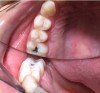

A 28-year-old woman, who previously had braces, had circumferential gumline decalcification (Figure 1) and wished to arrest lesions before they worsened (bitewing, Figure 2). The following protocol is consistent with the product instructions for the resin infiltration material from DMG America, which is the only commercially available resin infiltration system in the US.

Fig 1.  Circumferential gumline decalcification (Fig 1) and bitewing (Fig 2) of a 28-year-old woman.

Figure 1

Fig 2.  Circumferential gumline decalcification (Fig 1) and bitewing (Fig 2) of a 28-year-old woman.

Figure 2